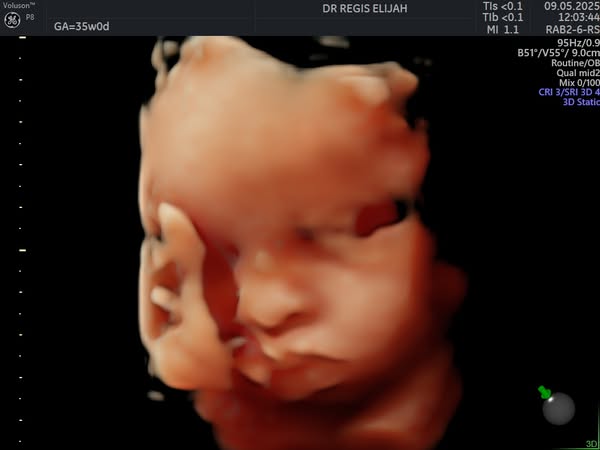

👶 Obstetrics Monday | 4D Ultrasound – See Your Baby in Real Time! 🧡

There’s nothing more magical than seeing your baby for the first time—and with our advanced 4D ultrasound technology, you don’t have to wait until delivery day to witness those precious moments!

At Elijah R OBGYN Women’s Clinic, our 4D pregnancy scans allow expectant parents to view their baby’s movements, facial expressions, and little kicks in real time, creating a powerful bonding experience.